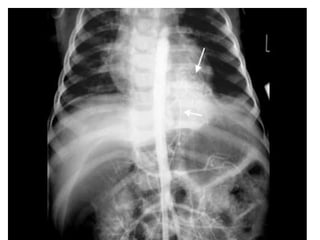

CT scan shows multiple large cysts (>2cm) involving the lower lobe of left lung.The cysts

are air-filled, expand the lower lobe, cause mediastinal shift and hypoplasia of right lung